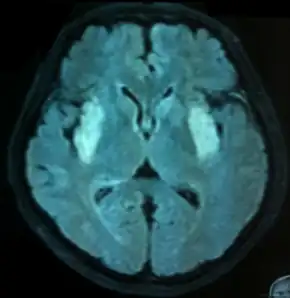

About half of cases are associated with tumors, most commonly teratomas of the ovaries.[1][4] Another established trigger is herpesviral encephalitis, while the cause in others cases is unclear.[1][4][5] The underlying mechanism is autoimmune with the primary target the GluN1 subunit of the N-methyl D-aspartate receptors (NMDAR) in the brain.[1][6] Diagnosis is typically based on finding specific antibodies in the cerebral spinal fluid.[1] MRI of the brain is often normal.[2] Misdiagnosis is common.[6]